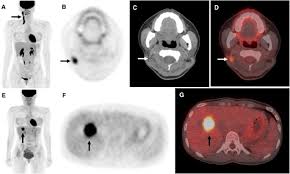

A pet scan can help detect which parts of the heart have been damaged or scarred, and it can help identify circulation problems in the. Pet scans use radioactively tagged molecules (or tracers) to image a wide array of molecular processes and when detected by a pet scanner, the tracers help your doctor to see how well your organs and tissues are working. Nuclear medicine images use a small quantity of a radioactive substance to detect, evaluate, or treat various diseases. Psma pet imaging is a fda approved scan with more precise detection of prostate cancer for better treatment planning and targeted care. These diseases include cancers, heart disease, endocrine, gastrointestinal or neurological.

A pet scan is not specific for cancer. It also can let you and your doctors know if cancer treatment is working. The scanner detects diseased cells that absorb. With that being said, not all cancers can be detected by pet. A pet scan, which uses a small amount of radioactive material, can help show if an enlarged lymph node is cancerous and detect cancer cells throughout the body that may not be seen on a ct scan. Positron emission tomography (pet) imaging scans use a radioactive tracer to check for signs of cancer, heart disease and brain disorders. The pet scan detects the concentrated psma tracer, pinpointing these tumors for more effective treatment. Psma pet imaging is a fda approved scan with more precise detection of prostate cancer for better treatment planning and targeted care. Most pet scans use a type of radiolabeled sugar to detect the cancer, as the majority of cancers grow quickly and need sugar for that growth. Pet can detect extremely small cancerous tumors, subtle changes of the brain and heart, and give doctors important early although cancer spreads silently in the body, pet can inspect all organs of the body for cancer in a single examination. Pet scans, short for positron emission tomography, can detect areas of cancer by obtaining images of the body's cells as they work. Ultrasound is also used to image the abdominal organs and kidneys. To determine whether the cancer has spread.

Those are detected by pet scanner and a computer converts a signal into detailed images showing how organs are working. Pet is speeding the detection of new drug weapons in the war on cancer. The tracer will collect in areas of. Positron emission tomography (pet) imaging or pet scan is a nuclear medicine imaging. Pet scans use radioactively tagged molecules (or tracers) to image a wide array of molecular processes and when detected by a pet scanner, the tracers help your doctor to see how well your organs and tissues are working. Pet scans are a type of test that create 3 dimensional (3d) pictures of the inside of your body. Pet scan is a special type of imaging test in which tracers are injected & are absorbed into organs of body and images are obtained. For cancer and disease detection, the most commonly used nuclear scan is an fdg pet scan. The pet scanner detects signals that are given off from the tracer. Pet/ct, which is a combination of positron emission tomography (pet) with computerized tomography (ct), is a powerful, essential tool for cancer detection and diagnosis. Diagnosis, cancer staging, treatment diagnosed with cancer and are undergoing active treatment, assess treatment response efficiency and perform cancer monitoring with pet/ct scan! A pet scan is not specific for cancer. With that being said, not all cancers can be detected by pet.